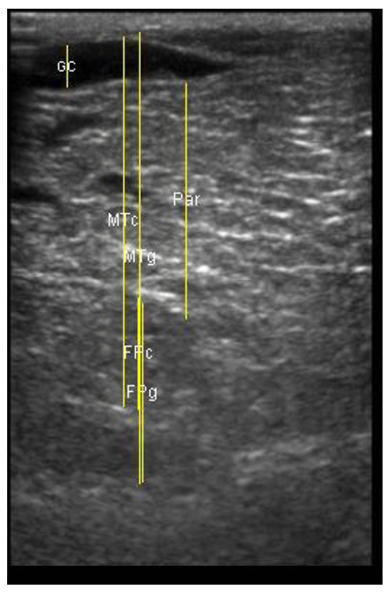

The image processing was undertaken using ImageJ software [28] as used by Abràmoff et al. [29]. The scales between pixels and millimetres were calculated based on the number of pixels, the scanning depth (mm), and the transducer width (mm) (Figure 4). This method relies on the ability of the operator to interpret and identify lines on the images. To standardize the assessment compartment depth, drawing templates were created for each time point as used by Molenaar et al. [30] and included four representative images from four different yearling ewes with and without the lines drawn for each compartment (Appendix A). The total depth of mammary gland conservative (MTc) was the smallest likely demarcation (abdominal wall) of the mammary gland (Figure 5a), and total depth of the mammary gland generous (MTg) was the largest likely demarcation of the mammary gland visible on the image [30] (Figure 5a). The MTc, MTg, fat pad (FP), parenchyma (PAR), and gland cistern (GC) depths were estimated at the deepest point for each sub-compartment, excluding the skin layers, using the straight tracer (Figure 5a) and were expressed in millimetres.

Figure 5.

(a) Demonstration of delimitations of the mammary total depth conservative (MTc) and generous (MTg), mammary gland cistern (GC), parenchyma (PAR) and the fat pad (FP) and (b) Demonstration of randomly positioning of regions of interest (1, 2, 3) in the parenchyma.